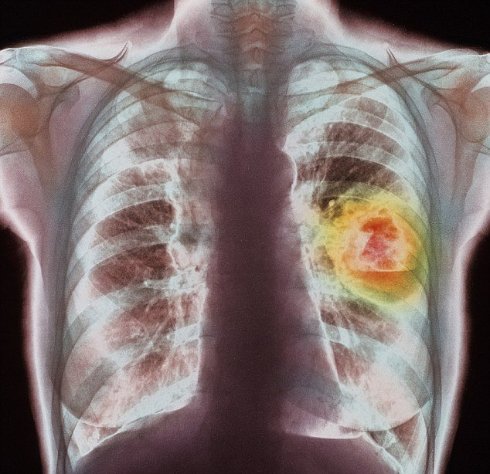

Кислород, которым мы дышим, может вызывать рак лёгких.

Авторами столь сенсационного заявления являются ученые из научно-исследовательского института Пенсильвании.

После множества проведённых исследований специалисты выяснили, что человек, проживающий довольно высоко над уровнем моря гораздо меньше рискует заболеть раком лёгких, в отличии, от человека, который проживает в непосредственной близости от моря.

Проанализировав скорость течения онкологических заболеваний различных органов, а также место постоянного проживания людей на различных высоких участках земной поверхности, эксперты пришли к выводу, на большой высоте содержится минимальное количество кислорода. Это значительно снижает темпы заболевания раком лёгких.